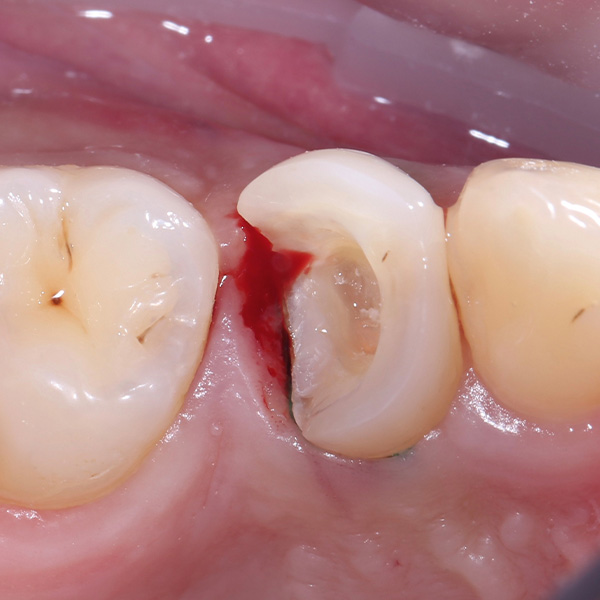

VITA ENAMIC multiColor Endokrone: Ausgangssituation vs. Finales Ergebnis

Ergebnis: VITA ENAMIC multiColor integrierte sich harmonisch in die natürliche Zahnsubstanz. Die insuffiziente Kompositfüllung an Zahn 14 (od) hatte zu Entzündungen im Zahnzwischenraum geführt.